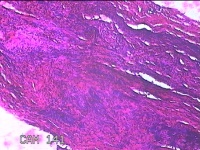

左耳部肿物

性别

男

年龄

24岁

临床诊断

一般病史

左耳部肿物1周。

标本名称

大体所见

灰白暗红色肿物1.3x1.2x0.2cm一个,表面糜烂。